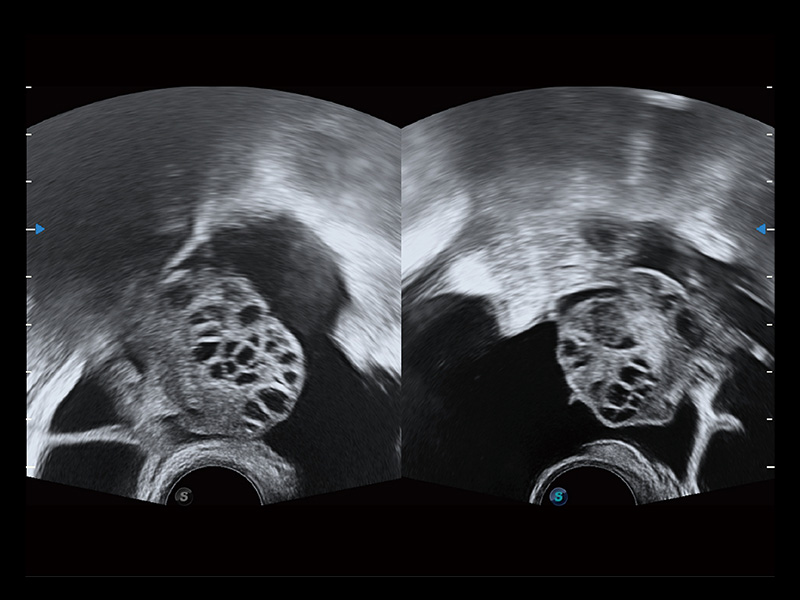

“生育问题”即关系民族复兴,也关系亿万家庭的幸福。随着婚育年龄推迟、社会压力增加等因素,越来越多人群也面临着“生不出、生不好”的问题。辅助生殖作为治疗不孕不育最有效的方法之一,也逐渐成为育儿新希望。而超声检查能为生殖需求人群的初诊评估提供宝贵的信息。 P20 Elite是球速体育入口匠心打造的一款生殖应用型彩超。她继承球速体育入口高端极光平台,突破性地将多款新型芯片及硬件模块进行整合,均衡了高端系统性能与小巧灵动机身。P20 Elite卓越的图像质量搭载专科探头,旨在为您提供全面的辅助生殖解决方案。

P20 Elite配备了丰富的生殖探头群和临床应用功能,在卵泡监测、穿刺取卵、胚胎移植、妊娠确认等领域,为生殖需求人群提供了新的临床机会,重新定义高端超声如何应用于生殖健康检查。

通过线上云会诊平台,实现县级医院与上级医院患者卵泡数据互联互通。避免重复性卵泡测量,提高诊断效率。